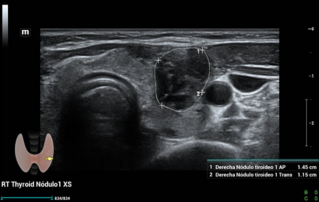

Ultrasound Journal 34 - Use of IOTA-ADNEX & O-RADS risk assessment models in MDT management of Adult Granulosa Cell Tumor

Comprehensive overview of granulosa theca cell tumors of the ovary, covering epidemiology, clinical presentation, diagnosis, treatment options, and prognosis for both adult and juvenile types.